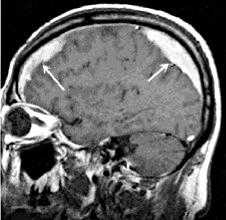

При МРТ выявлены обширная субдуральая гематома, распространяющаяся от лобной до затылочной области справа, смещение срединных структур влево на 16 мм, а также множественные каверномы головного мозга: небольшая кавернома, расположенная на конвекситальной поверхности правой лобной доли, и небольшая кавернома в полюсе левой лобной доли (рис. 1). Рис. 1. Больной П. МРТ при поступлении. Т1 (а), Т2 (б) — взвешенные изображения. Видна обширная острая субдуральная гематома справа и каверномы лобных долей: поверхностно расположенная кавернома правой лобной доли (источник кровоизлияния), кавернома полюса левой лобной доли. Смещение срединных структур влево до 16 мм. При электроэнцефалографии выявлены диффузные изменения, свидетельствующие о раздражении коры мозга. Отмечена межполушарная асимметрия за счет снижения амплитуды биопотенциалов, редукции альфа-ритма, преобладания негрубой медленной активности справа. Слева — доминирующие признаки раздражения коры с наличием негрубой эпилептиформной активности. Отмеченные изменения более выражены в височно-теменно-затылочных областях.